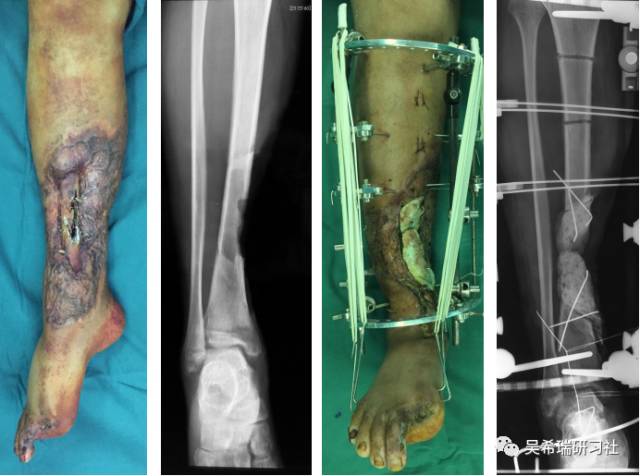

手术后40天外地转来胫骨外露感染骨坏死20cm胫前皮肤缺损腘动脉断裂腓总神经损伤足下垂

TIPS:第一次手术  清除病灶抗生素骨水泥填塞。远端整块水泥包裹外露骨质,近端连珠以便骨搬移钢丝克氏针张力缝合皮肤5天后下地部分负重走路联合骨牵引纠正足下垂15天后去除跟骨骨牵引针

TIPS:骨水泥40天后去除,半开放植骨因为有皮肤缺损,用骨水泥做成瓦片闭合伤口自体优质松质骨(如图)(半开放植骨的典范)皮肤采用了钢丝牵张闭合骨搬移+半开放植骨植骨后一个月去除瓦片骨水泥,创面新鲜钢丝克氏针张力闭合伤口加游离植皮继续骨搬移修整入院3个月腓总神经恢复